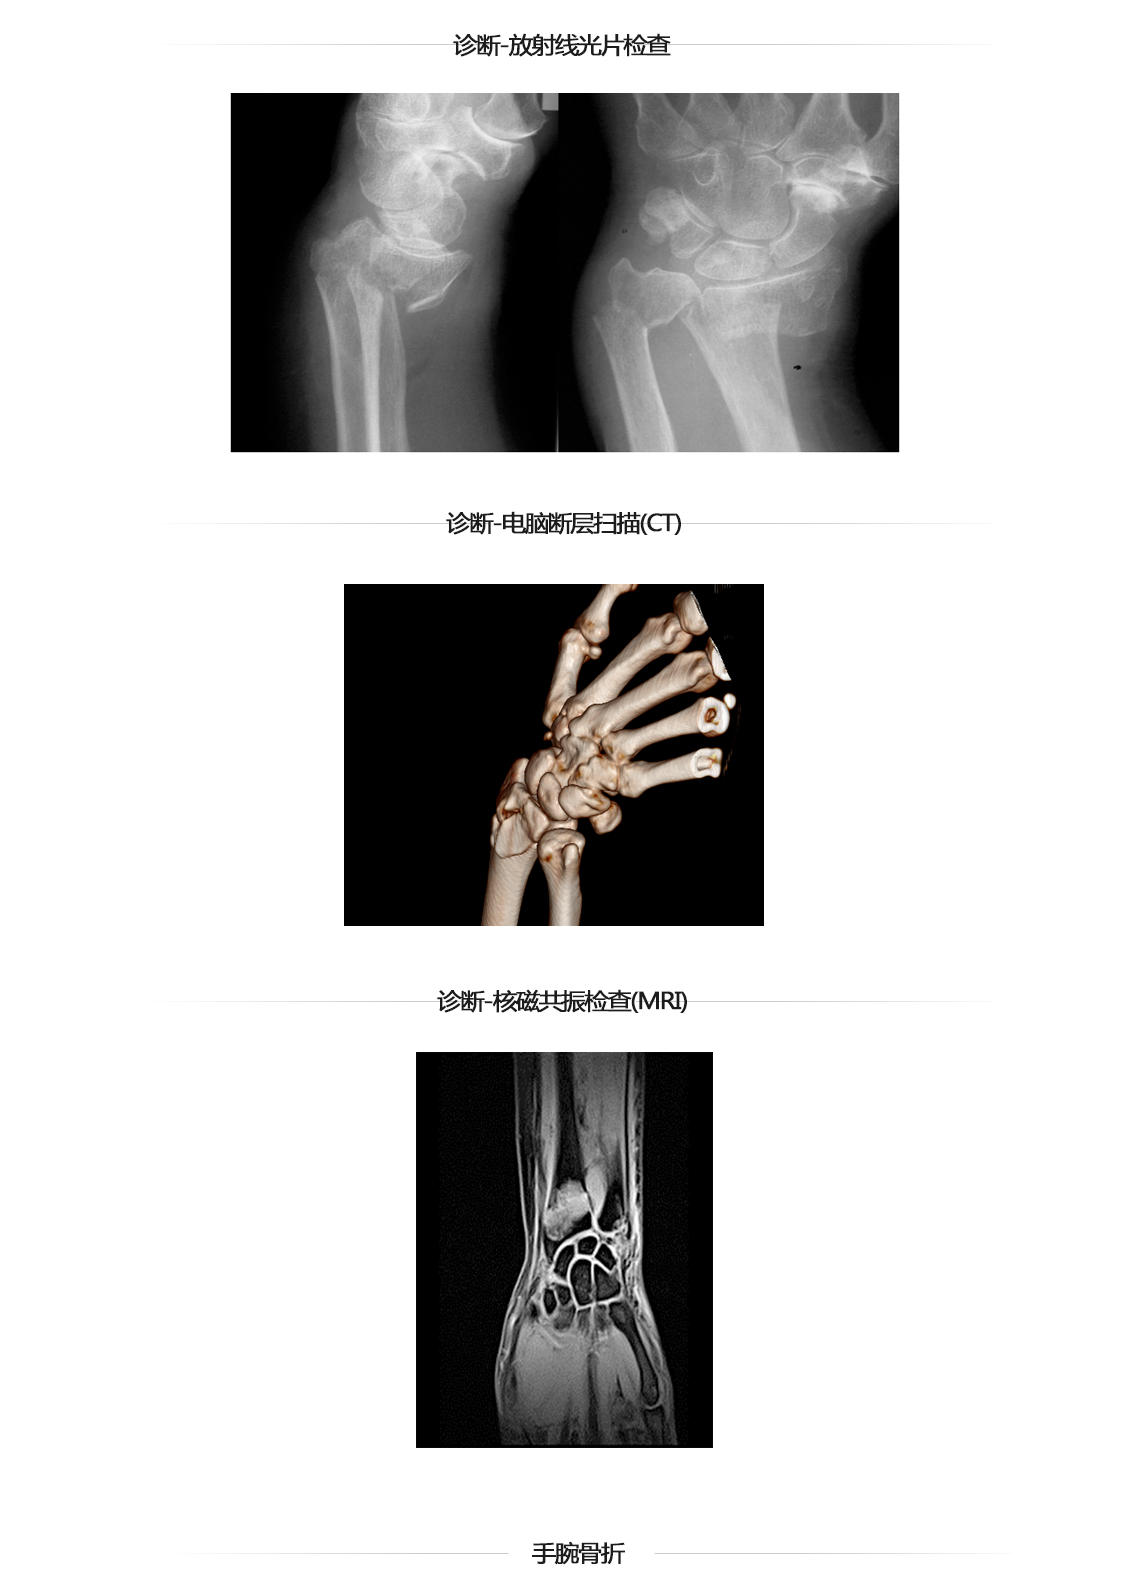

手腕关节骨折

手腕骨折